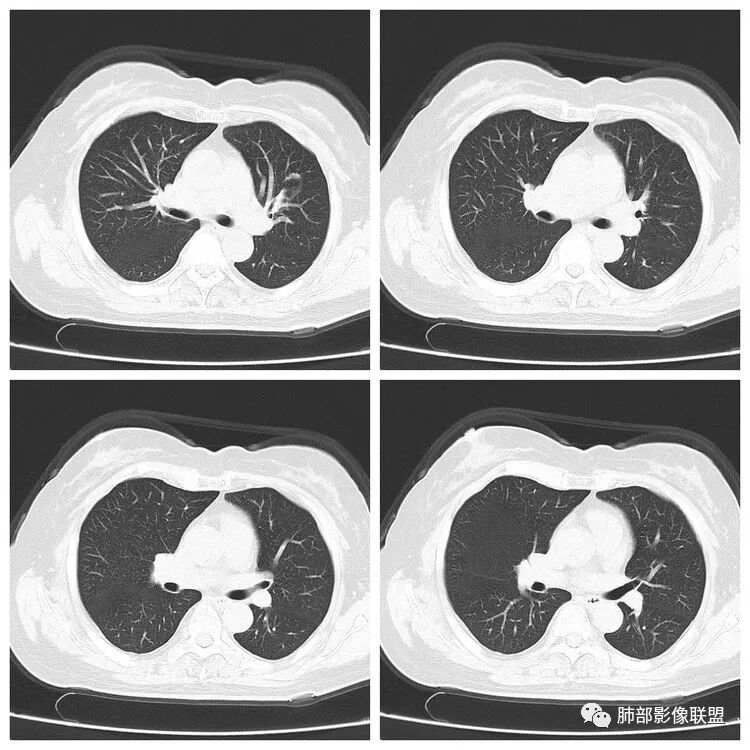

以下是两个时间点左右对比

2019.11.26  👇                           2020.01.20👇                                            2019.11.26片

2020.01.20片

1.老年女性,咳嗽咳痰一月,伴咯血及痰中带血,多为咳白痰,无发热,炎性指标不高,且抗炎治疗,两月后病灶未见明显吸收和改变,普通病原体感染不支持。

2.早期CT表现左肺上叶不规则团块影,呈混合密度,以实性密度为主,但整体密度偏低,周围隐约见磨玻璃密度影。

边缘不规则,前内侧缘见小叶间隔限制(注意,并非典型深分叶),病灶外侧细长毛刺,病灶内有小空泡及空气支气管征,有胸膜牵拉征象。

上述征象均提示病灶为恶性病灶,但边缘特征及空气支气管征似乎有别于常见的浸润性腺癌及MALT。

3.复查影像显示病灶整体大小变化不明显,其内空泡消失,但是周围磨玻璃影趋于似清非清,整体病灶收缩力中等偏弱,均提示粘液腺癌的可能性大。